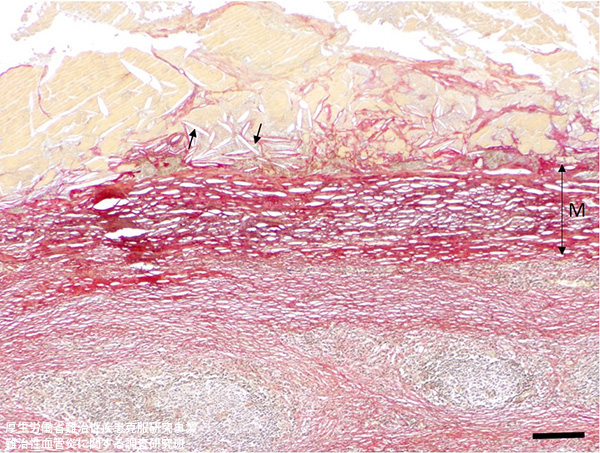

内膜の粥腫は軟化、崩壊をきたし、コレステリン裂隙を認める(→)。中膜では平滑筋細胞が脱落し、弾性線維が断裂消失して線維組織により置換されている。(EVG染色) Bar=200 μm、M: 中膜